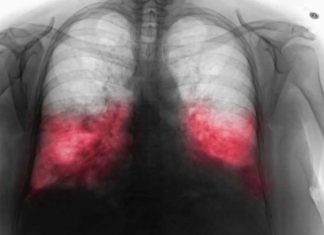

VELlKl BR0J ZARAŽENIH H0DAJUĆ0M UPALOM PLUĆA: Ako imate ove simptome 0DMAH...

Hodajuća upala pluća: Tih neprijatelj zdravljaU ovom članku istražujemo hodajuću upalu pluća, bolest koja često prolazi ispod radara zbog svojih blagih simptoma. Iako se...